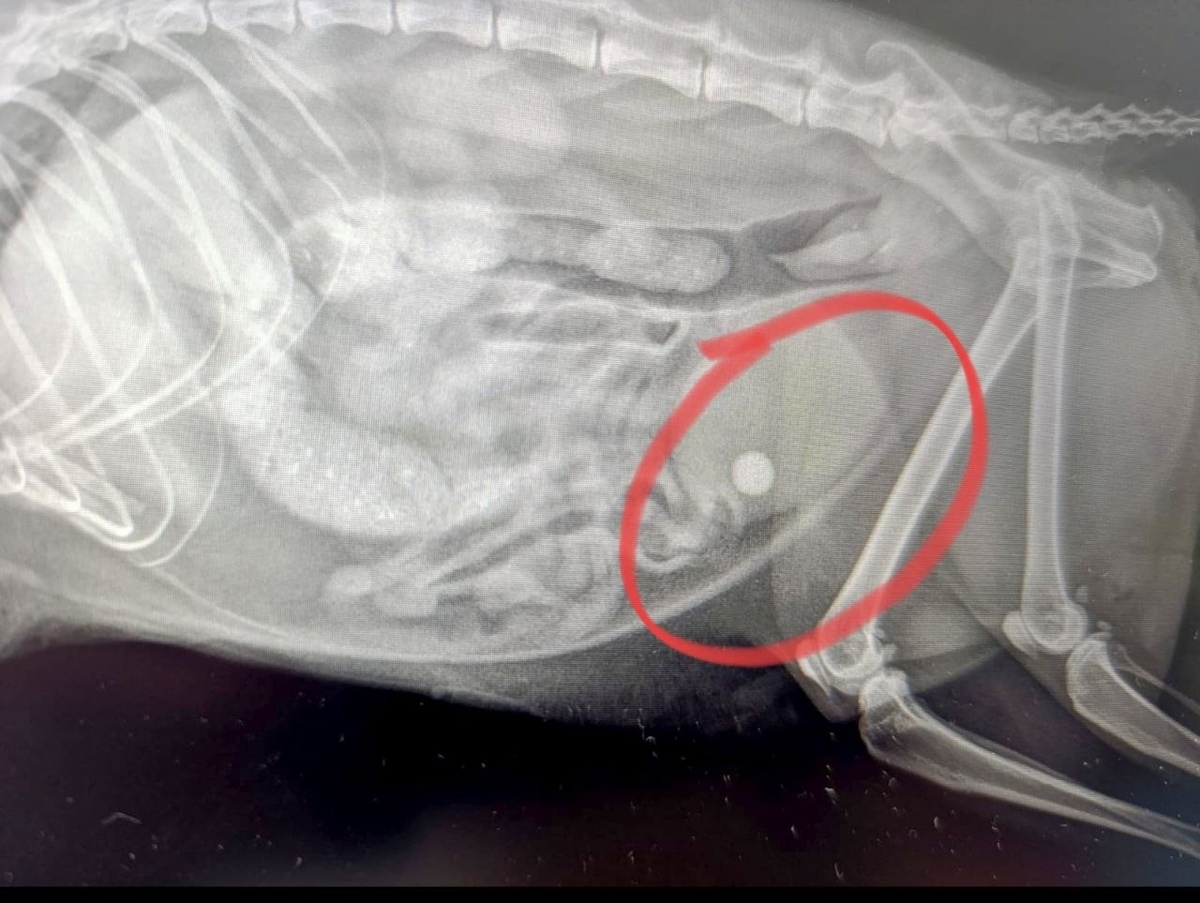

Красотка кошка была в срочном порядке прооперирована нашими врачами. 💊К сожалению, мочекаменная болезнь - заболевание, которое очень часто встречается у котов и кошек. Кошке была проведена цистотомия — хирургическая операция по вскрытию мочевого пузыря, проводимая под общим наркозом, для удаления камней. 🐱После операция киса несколько дней наблюдалась в условиях нашего стационара и была выписана домой. 😻Уролог - Атаева Марина Владимировна 😻Хирург - Юмашева Светлана Павловна